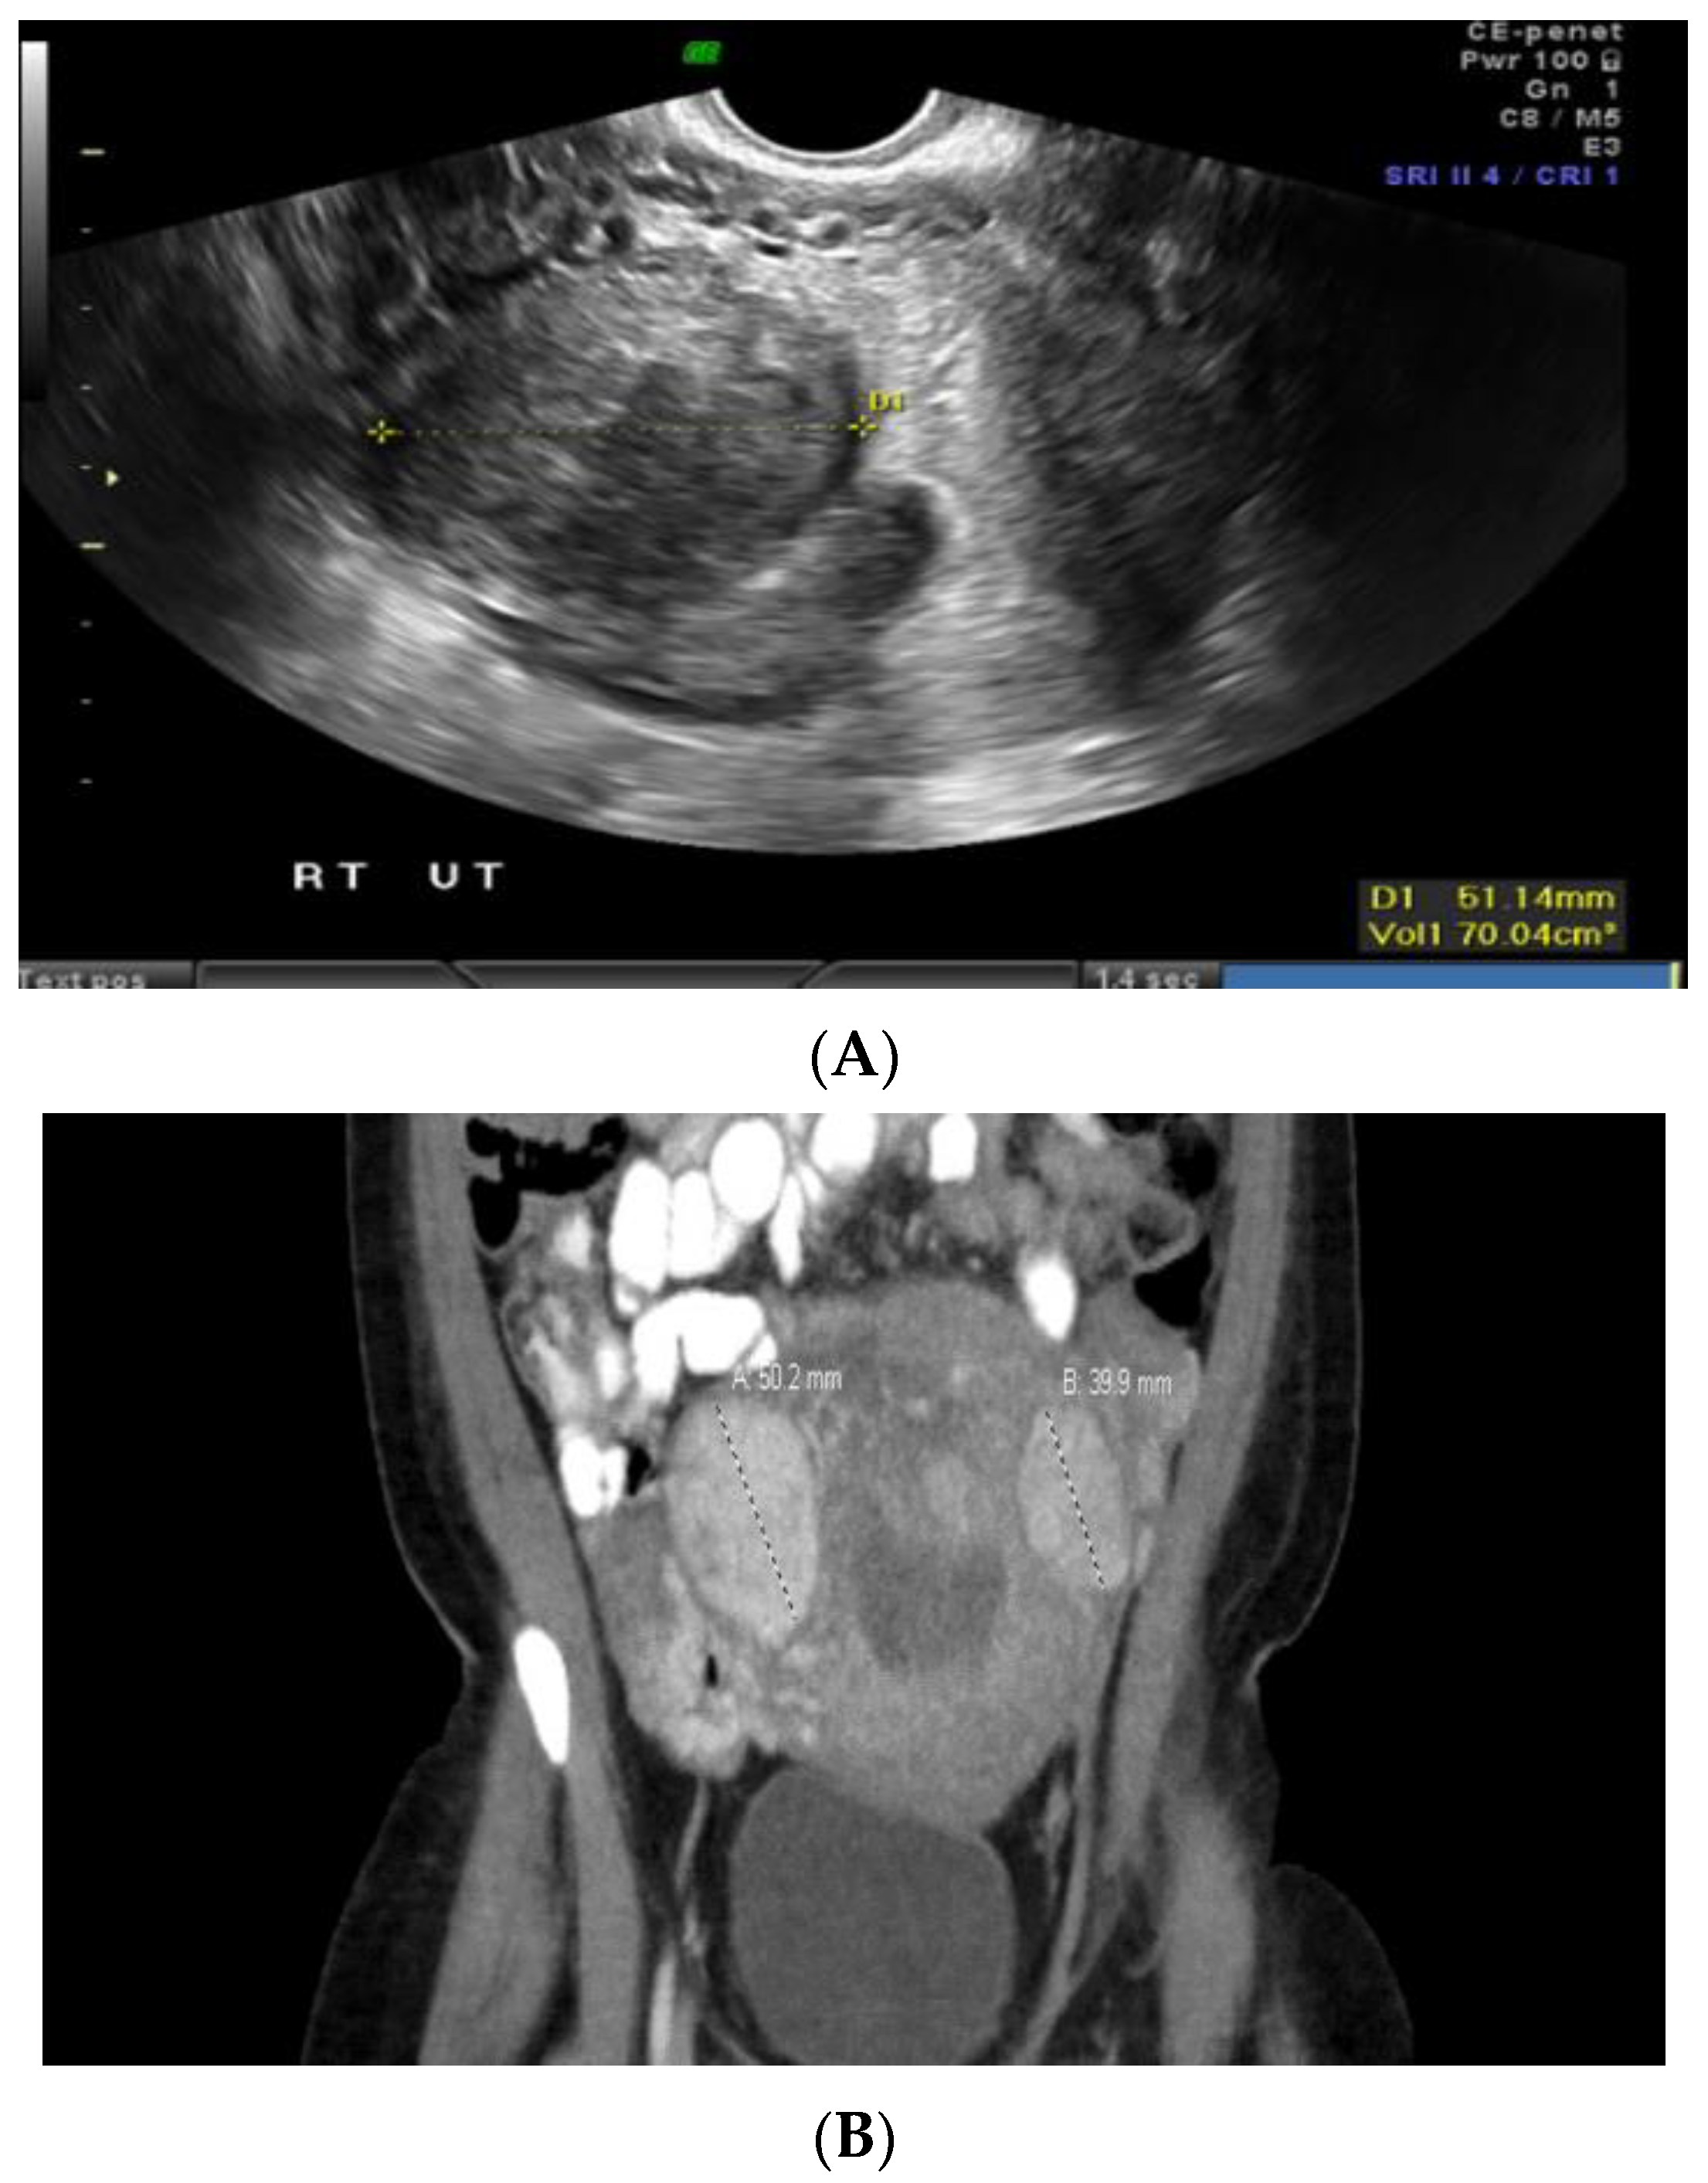

Case 2: A 34-year-old Black patient with a personal history of uterine fibroid and a family history of various cancers had an 8 cm submucosal uterine fibroid (Figure 2A). She underwent a total abdominal hysterectomy, left salpingo-oophorectomy, and right salpingectomy. Pathology revealed a leiomyoma with features of FH deficiency. Germline genetic testing showed a mutation in the NTHL1 gene, which is not associated with leiomyomas or an increased risk for cancer, and a variant of uncertain significance in the FH gene, c.1055G>A (p.Gly352Asp). This specific missense change, guanine to adenine at nucleotide position 1055, results in an amino acid change from glycine to aspartic acid at codon 352. At the time, there was not enough evidence to know whether this change disrupts protein function; this specific missense variant had not been reported by other laboratories, nor had it been reported in the literature in individuals with FH-related conditions. However, given the family history of renal cancer, the patient was advised to undergo screening for this malignancy. A subsequent abdominal ultrasound and computed tomography (CT) scan revealed a large mass extending from the left kidney (Figure 2B). A needle core biopsy showed a high-grade renal cell carcinoma with papillary features, suggestive of FH-deficient renal cell carcinoma. The patient underwent radical left nephrectomy and adrenalectomy, which confirmed high-grade renal cell carcinoma with poorly differentiated areas and focal sarcomatoid spindle cell change, suspicious for FH-deficient renal cell carcinoma. Left retroperitoneal lymph nodes were diffusely involved by metastatic renal cell carcinoma.

Figure 2.

(A) Submucosal uterine fibroid. (B) Computed tomography (CT) scan-coronal section abdomen.